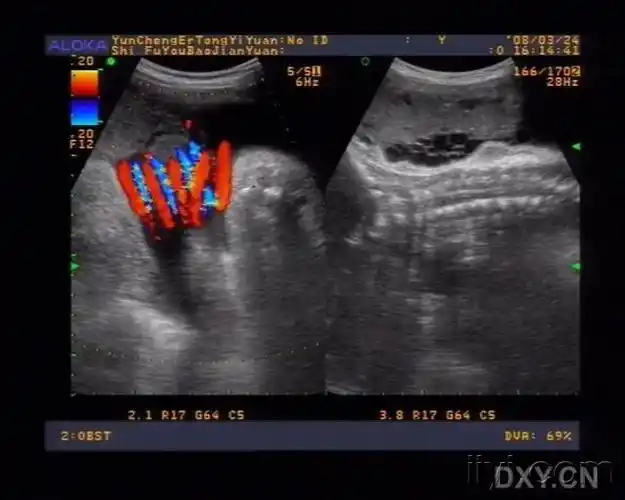

看这个宝宝的脐带绕颈多经典! - 超声医学讨论版 - 爱爱医医学论坛

超声诊断脐带缠绕

脐带缠绕超声如图所示:脐带绕颈对胎儿的影响视其缠绕松紧程度而不同

看胎儿的b超图像,胎儿的颈部会有u型压迹,超声提示会备注胎儿脐带绕颈